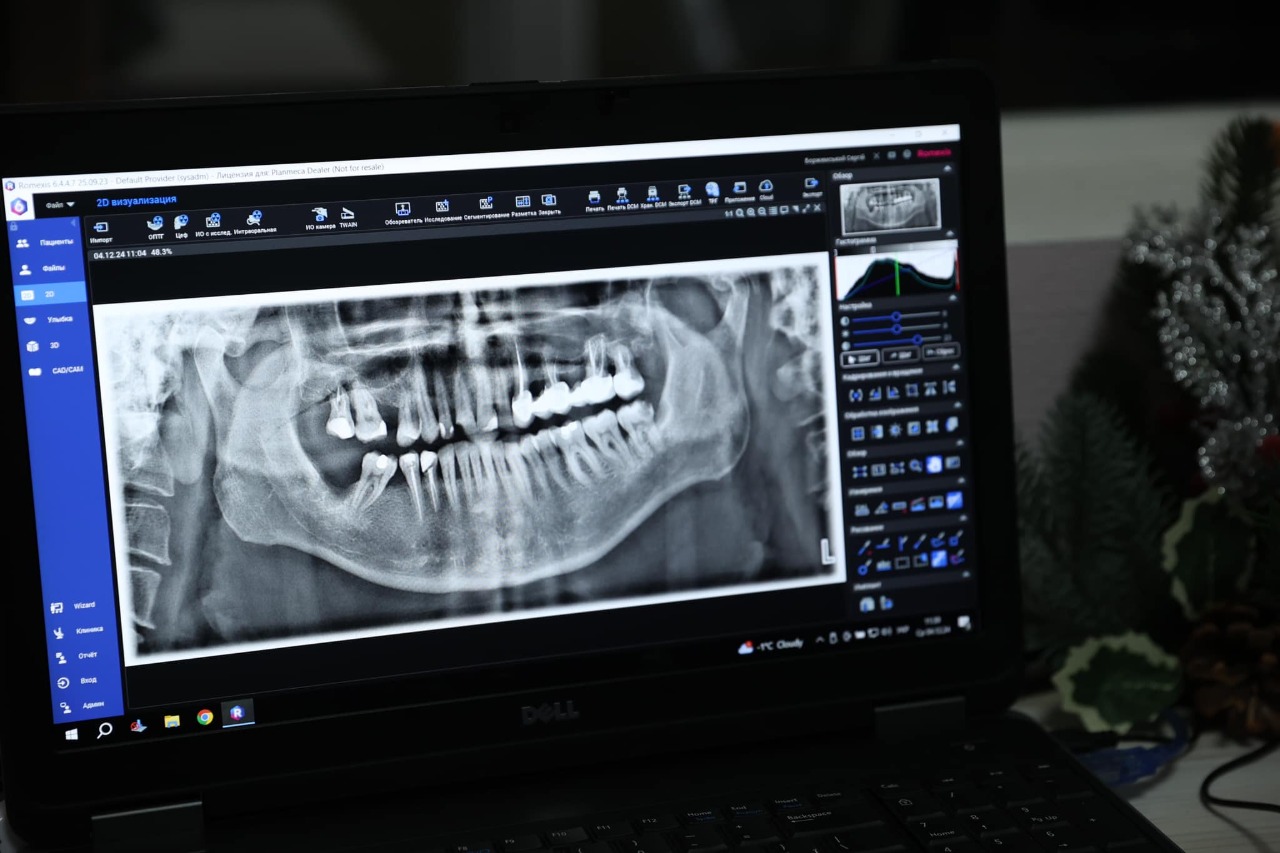

Пацієнти тепер можуть отримувати панорамні рентген-знімки прямо в центрі. Дані автоматично передаються лікарю через єдину мережу, що значно економить час і дозволяє провести всі процедури в одному місці.